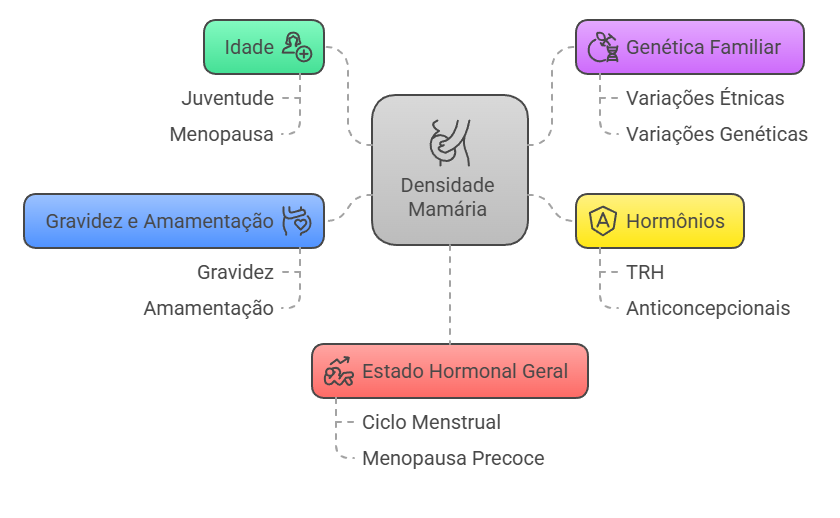

Fatores que Influenciam a Densidade Mamária ao Longo da Vida

A densidade mamária não é uma característica fixa – ela se modifica naturalmente durante nossa vida, respondendo a diversos fatores internos e externos. Compreender essas variações ajuda a entender melhor seu próprio corpo e as mudanças que você pode observar ao longo dos anos.

Idade: A Principal Influenciadora

A idade é o fator mais significativo nas mudanças da densidade mamária.

– Durante a juventude e idade reprodutiva (20-40 anos), as mamas são naturalmente mais densas devido à alta atividade hormonal, com níveis elevados de estrogênio e progesterona mantendo o tecido glandular bem desenvolvido.

– Na transição para a menopausa (40-50 anos), a densidade começa a diminuir gradualmente devido às flutuações hormonais.

– Após a menopausa (acima de 50 anos), ocorre redução significativa da densidade, pois o tecido glandular é substituído por tecido adiposo em um processo natural chamado “involução mamária”, tornando a mamografia mais fácil de interpretar.

Genética Familiar: Sua Herança Biológica

Assim como a altura ou a cor dos olhos, a tendência à densidade mamária também é herdada.

Se sua mãe e irmãs têm mamas densas, você provavelmente também terá. Estudos mostram variações étnicas, com mulheres asiáticas tendendo a manter maior densidade por mais tempo comparado às caucasianas. Certas variações genéticas influenciam como os hormônios afetam o tecido mamário, mas a genética não é determinante absoluto, pois outros fatores ambientais e hormonais podem modificar sua densidade ao longo da vida.

Hormônios: Os Grandes Reguladores

Os hormônios exercem influência direta sobre a densidade mamária.

– A Terapia de Reposição Hormonal (TRH) pode manter ou aumentar a densidade mamária após a menopausa, especialmente quando combina estrogênio e progesterona, com efeitos que podem persistir por anos após interromper o tratamento.

– Anticoncepcionais hormonais causam discreto aumento temporário da densidade, principalmente em mulheres jovens, sendo o efeito reversível e variável conforme a formulação.

– Tratamentos hormonais para fertilidade também podem temporariamente aumentar a densidade devido aos altos níveis hormonais, normalizando-se após o fim do tratamento.

Gravidez e Amamentação: Transformações Naturais

Estes são períodos de mudanças dramáticas na mama:

Diversos aspectos do seu estado hormonal influenciam a densidade:

– Durante a gravidez, ocorre aumento significativo do tecido glandular para preparar a produção de leite, elevando consideravelmente a densidade (especialmente no primeiro trimestre) e tornando as mamas mais sensíveis e volumosas.

– Durante a amamentação, o tecido glandular permanece em máxima atividade com densidade elevada, sendo normais as alterações constantes na textura e volume.

– Após o desmame, inicia-se a “involução pós-lactação”, onde o tecido glandular diminui gradualmente, podendo resultar em densidade menor que o período pré-gravidez, especialmente em mulheres que amamentaram por períodos prolongados.

Estado Hormonal Geral: Flutuações Constantes

A densidade mamária pode variar sutilmente durante o ciclo menstrual, com alguns estudos sugerindo maior densidade na segunda fase (após ovulação).

Mulheres que entram em menopausa precoce (antes dos 45 anos) tendem a ter redução mais rápida da densidade.

Condições como síndrome dos ovários policísticos (SOP), distúrbios da tireoide e uso de alguns medicamentos (como antidepressivos) também podem influenciar indiretamente a densidade mamária através de alterações hormonais.